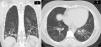

En los exámenes de laboratorio de diciembre del 2020 se evidenció: leucocitosis ligera, función renal normal, uroanálisis sin alteraciones, perfil lipídico normal, función tiroidea normal, leve elevación de la creatincinasa total y de la aldolasa, además de elevación de las transaminasas. La radiografía de tórax de octubre del 2020 presentaba opacidades en vidrio esmerilado de distribución periférica en ambos campos pulmonares. En diciembre del 2020 se realizó una tomografía de tórax (TACAR) con hallazgos de parches de vidrio esmerilado de distribución periférica y aleatoria en ambos campos pulmonares, con compromiso aproximado del 20% del parénquima pulmonar. El perfil inmune se presenta en la tabla 1. Durante su hospitalización de diciembre del 2020 se realizó un ecocardiograma transtorácico, sin alteraciones, en tanto que en la caminata de 6min se observó una caída de la saturación de oxígeno (SatO2) durante el ejercicio como único hallazgo patológico. La espirometría con curva flujo volumen encontró un volumen espirado forzado en el primer segundo (VEF1), con disminución de moderada a severa y capacidad vital forzada (CVF) normal.

Tomografía de tórax con hallazgos de EPI. Tomografía de tórax en corte coronal (A) y axial (B). Se evidencia vidrio esmerilado de distribución peribroncovascular, con mayor afectación de segmentos posteriores y lóbulos inferiores, donde se identifican reticulación, bandas parenquimatosas, engrosamiento de paredes bronquiales y bronquiectasias de tracción con pérdida de volumen asociada, debido a retracción de cisuras. Hallazgos compatibles con patrón de NINE fibrótica. Extensión calculada del 30%.